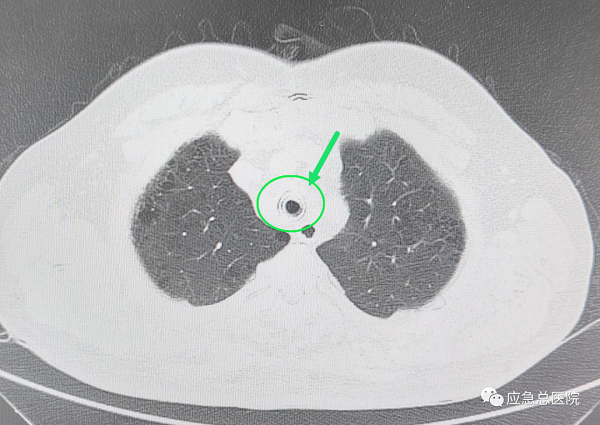

全身麻醉下,王洪武教授应用王氏插入法,仅5秒钟就成功插入硬质镜,建立了治疗和抢救通道,电子支气管镜下,可以看见原来的裸支架已经埋入气管粘膜内,突入的组织使得管腔仅有20%的空间能够流通空气,在张楠教授等专家的协助下,应用硬镜铲切、硬镜扩张、ND-YAG激光、高频电、氩气刀、二氧化碱冻取、球套扩张等多种技术配合,切除气管内增生的肉芽组织、部分异常粘膜,将原裸支架烧断、分解,抽丝剥茧,最后将整个支架完整取出,气管狭窄程度减轻为50%,手术结束后患者迅速苏醒,感到憋气症状明显缓解。